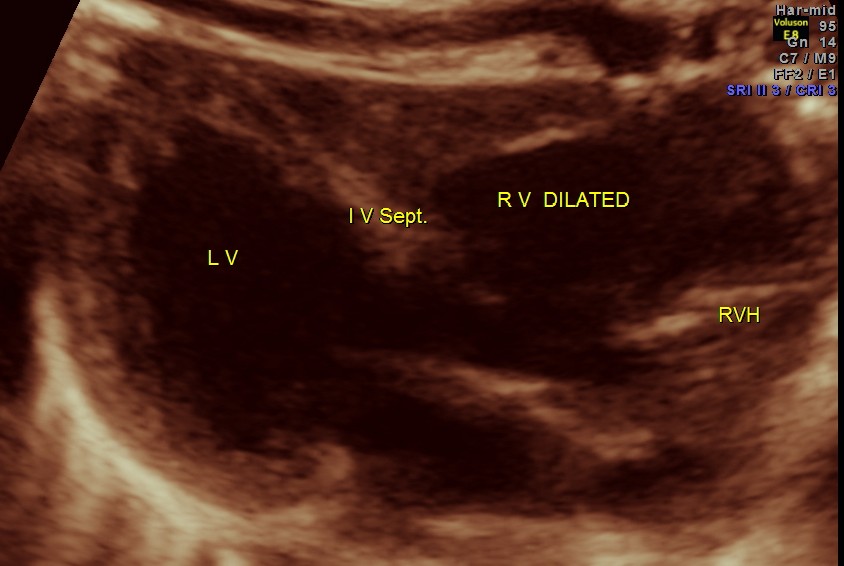

The following pictures are of the heart of the child .

The IVS straddling the aorta is prominently seen ; The RV is mildly dilated . Though the pulmonary artery was difficult to comment on , I would still go with TETRALOGY OF FALLOT with RENAL DYSPLASIA , which makes it complicated.